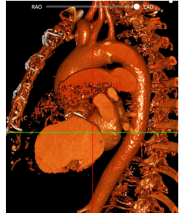

主动脉瓣环周长:97.8mm(瓣上3mm结构周长89mm);

左室流出道周长:92.9mm;

左冠开口高度:17.0mm,左冠瓣长:15.7mm;

右冠开口高度:14.0mm ,右冠瓣长:16.3mm;

主动脉窦宽:43.7-45.3mm;

STJ周长:152.5mm,STJ高度:22.2mm;

升主动脉周长:166.6mm,最大直径54.5mm;

入路:血管情况一般,直径均在7mm以上,但整体均有钙化需要注意;

右侧为主入路,左侧为辅;

升主扩张:平均53mm,最大54.3mm;

三叶瓣:瓣叶无增厚,左右钙化粘连,瓣上可推开空间受限;

左右冠风险较低:术中使用26mm球囊预扩,选用TAV30。